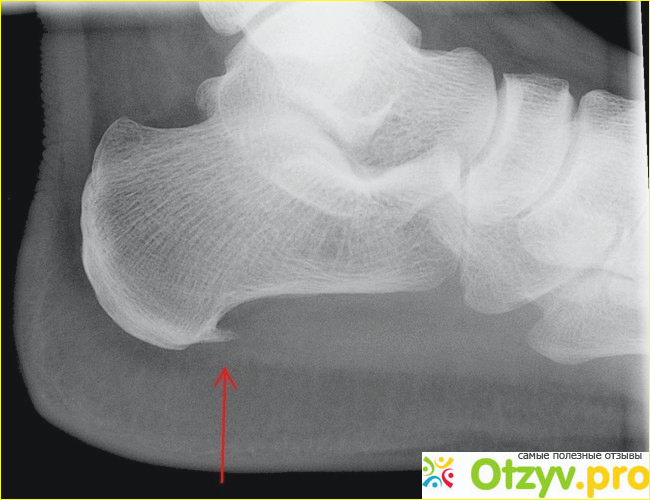

Под пяточной шпорой понимают не инфекционное воспаление плантарной фасции, в следствие чего это заболевание по-научному называют плантарный фасциит. Воспаление плантарной фасции происходит из-за чрезмерного давления на нее человеческого тела и пяточной кости. В самом начале течения заболевания происходит только воспаление, а костный нарост образуется уже после из-за чрезмерного отслаивания кальция в месте воспаления. Таким образом получается нарост на пяточной кости, он все сильнее давит на фасцию и по своему внешнему виду напоминает шпору. Поэтому, в народе этот недуг окрестили пяточной шпорой.

Когда человек ощущает боль в пятке, следует сразу обратиться в ортопеду, чтобы правильно установить диагноз, ведь существует множество заболеваний, характеризуемых болью в пятке. Доктор назначит рентген, на котором будет видно, есть шпора или нет и назначит соответствующее лечение.